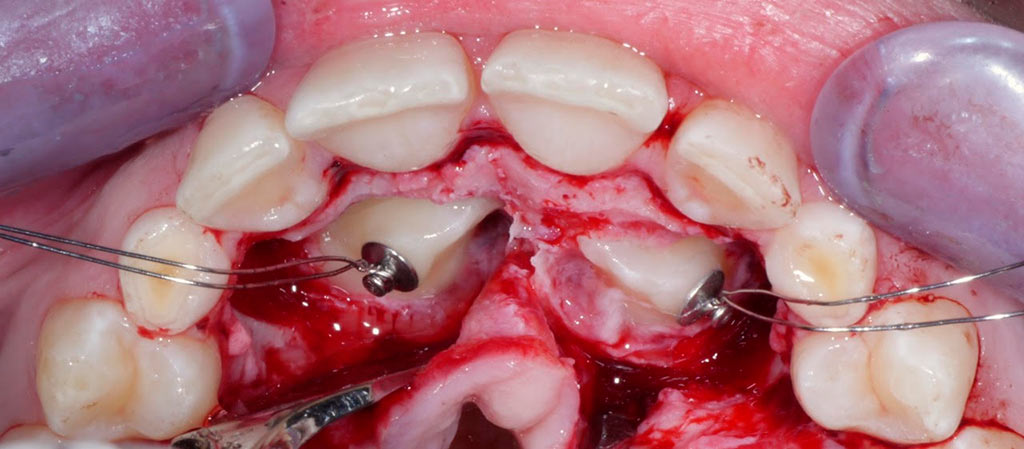

Tenemos una amplia experiencia en cirugía bucal, con tratamientos de extracción de molares del juicio, caninos incluídos, quistes, apicectomías, frenectomías, extirpación de mucoceles.

Tracción de canino con k9